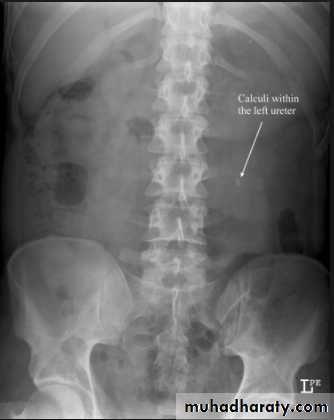

- Over 90% of calculi are radiopaque on plain films and virtually all on CT as very sensitive for detection of calculi, even those that appear radiolucent on plain film.- Most of these stones are a mixture of calcium oxalate and phosphate.

- Only pure uric acid and xanthine stones are radiolucent on plain x-ray but CAN be identified by CT or US , uric acid stones are associated with increased uric acid excretion in urine as in gout.

-Plain film may be useful in demonstrating calculi. -After contrast injection: Acutely obstructed kidney shows a dense nephrogram (dense opacification of the renal parenchyma).

then the level and degree of obstruction can be determined as dilated pelvi-caliceal system and ureter are followed down to the point of obstruction (point of hold up).